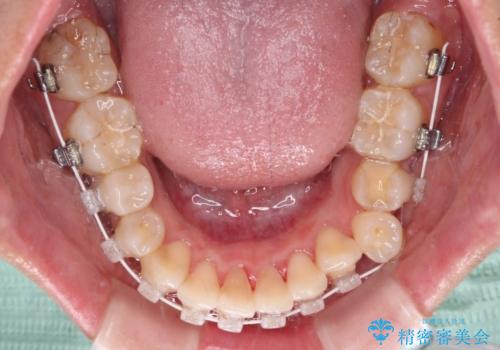

- 下顎の歯列から飛び出した小臼歯を気にして来院された患者様です。

歯列以外に、上顎左右側切歯が矮小歯であり、上顎4前歯は失活していたため、矯正治療で歯列を整えるとともに上顎前歯の幅を調整し、矯正治療後にオールセラミッククラウンにて審美歯科治療を行うこととしました。

矯正治療は、小臼歯1本分を歯列に納めないいけない状態であったため、表側のワイヤー装置にて行うこととしました。